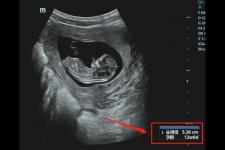

孕期夜醒,老公的手機閃爍不停,我打開一看,竟是一個女孩發來問,睡了嗎?而聊天記錄是空的,我全身起了雞皮,長吸口氣回了句,還沒。看著“對方正在輸入”我的心砰砰跳,終於她回復了,而我肚子一陣劇痛。

自那次後,我夜夜失眠,閉上眼睛全是他和那個女人膩歪的畫面。我仿佛上癮,趁他睡著不停翻他手機,可是越看我越痛苦。我多想把手機砸到他臉上叫他滾蛋,可是我摸著自己的肚子,特別茫然,孩子怎麽辦?我不想孩子沒有爸爸,可是他做的事真的讓我很難受,該怎麽辦?